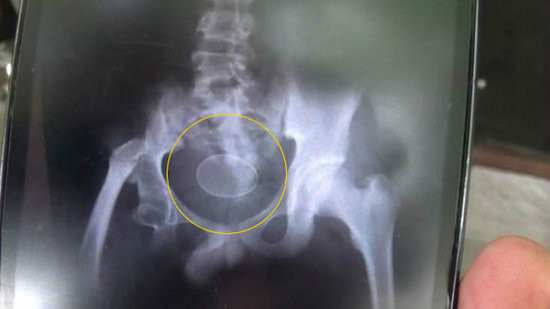

广州日报讯(记者林洪浩)凌晨,广州中医药大学附属第一医院送来一位中年男病人,病人从外表看来没有任何受伤迹象,但表情非常奇怪,指着肛门做痛苦状,医生一拍CT吓了一跳,病人的肛门竟然被塞进一根手电筒一样的异物,经过两个小时的手术才把异物取出来。